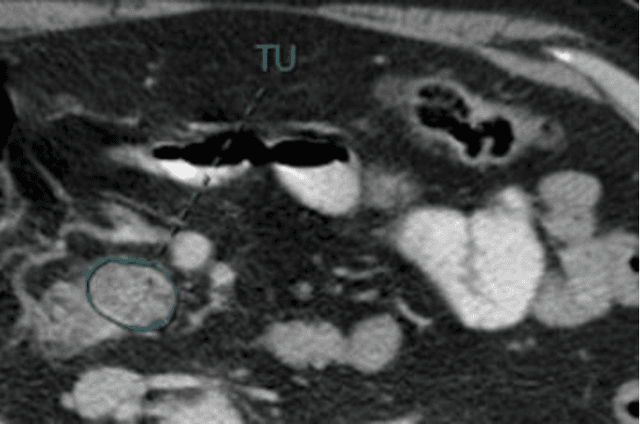

Abstract:As an analytic pipeline for quantitative imaging feature extraction and analysis, radiomics has grown rapidly in the past a few years. Recent studies in radiomics aim to investigate the relationship between tumors imaging features and clinical outcomes. Open source radiomics feature banks enable the extraction and analysis of thousands of predefined features. On the other hand, recent advances in deep learning have shown significant potential in the quantitative medical imaging field, raising the research question of whether predefined radiomics features have predictive information in addition to deep learning features. In this study, we propose a feature fusion method and investigate whether a combined feature bank of deep learning and predefined radiomics features can improve the prognostics performance. CT images from resectable Pancreatic Adenocarcinoma (PDAC) patients were used to compare the prognosis performance of common feature reduction and fusion methods and the proposed risk-score based feature fusion method for overall survival. It was shown that the proposed feature fusion method significantly improves the prognosis performance for overall survival in resectable PDAC cohorts, elevating the area under ROC curve by 51% compared to predefined radiomics features alone, by 16% compared to deep learning features alone, and by 32% compared to existing feature fusion and reduction methods for a combination of deep learning and predefined radiomics features.

Abstract:Cox proportional hazard model (CPH) is commonly used in clinical research for survival analysis. In quantitative medical imaging (radiomics) studies, CPH plays an important role in feature reduction and modeling. However, the underlying linear assumption of CPH model limits the prognostic performance. In addition, the multicollinearity of radiomic features and multiple testing problem further impedes the CPH models performance. In this work, using transfer learning, a convolutional neural network (CNN) based survival model was built and tested on preoperative CT images of resectable Pancreatic Ductal Adenocarcinoma (PDAC) patients. The proposed CNN-based survival model outperformed the traditional CPH-based radiomics approach in terms of concordance index by 22%, providing a better fit for patients' survival patterns. The proposed CNN-based survival model outperforms CPH-based radiomics pipeline in PDAC prognosis. This approach offers a better fit for survival patterns based on CT images and overcomes the limitations of conventional survival models.

Abstract:Pancreatic ductal adenocarcinoma (PDAC) is one of the most aggressive cancers with an extremely poor prognosis. Radiomics has shown prognostic ability in multiple types of cancer including PDAC. However, the prognostic value of traditional radiomics pipelines, which are based on hand-crafted radiomic features alone, is limited due to multicollinearity of features and multiple testing problem, and limited performance of conventional machine learning classifiers. Deep learning architectures, such as convolutional neural networks (CNNs), have been shown to outperform traditional techniques in computer vision tasks, such as object detection. However, they require large sample sizes for training which limits their development. As an alternative solution, CNN-based transfer learning has shown the potential for achieving reasonable performance using datasets with small sample sizes. In this work, we developed a CNN-based transfer learning approach for prognostication in PDAC patients for overall survival. The results showed that transfer learning approach outperformed the traditional radiomics model on PDAC data. A transfer learning approach may fill the gap between radiomics and deep learning analytics for cancer prognosis and improve performance beyond what CNNs can achieve using small datasets.